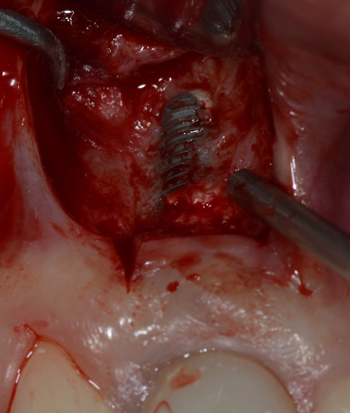

Após dois dias de uso do antibiótico, antes da cirurgia, a fístula havia regredido (Figura 2). O acesso cirúrgico foi feito através de uma incisão na linha mucogengival (Figura 3).

Em seguida, o tecido mole inflamado ao redor do implante foi removido e a superfície do implante jateada com spray de bicarbonato de sódio sob alta pressão, durante um minuto (Figura 4A), para descontaminação.

Figura 3 – Acesso cirúrgico à área da lesão periapical.

Figuras 4 – A. Jateamento da superfície do implante com spray de bicarbonato de sódio sob alta pressão. B. Enxerto com osso mineral bovino. C. Colocação da barreira de membrana para promoção de regeneração óssea guiada.